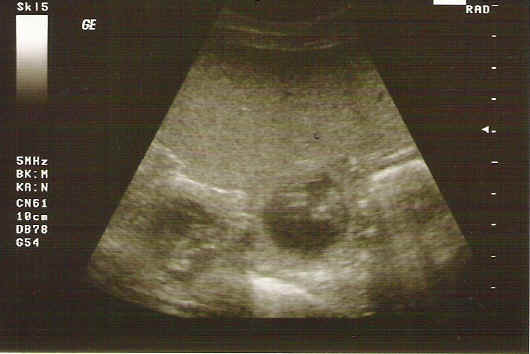

Brisby van Noort Ultraschallbilder " D - Wurf "

Vater: Broncor v. Speichersee Mutter: Brisby van Noort

Ultraschallbilder der Hündin Brisby van Noort, erstellt am 28. Tag.